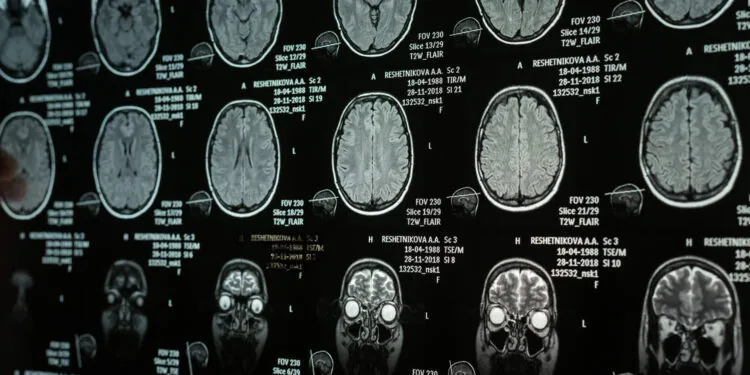

最近の研究によると、特定の脳領域の物理的構造が、自己愛的な性格特性と感情を隠す習慣を結びつける役割を果たしていることが明らかになった。研究者らは、健康な成人の脳スキャンを調べた結果、前部島皮質の体積と表面の折り畳みが、自